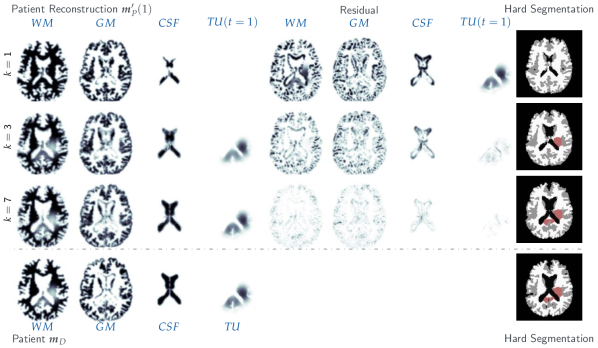

Setup. For both atlas and patient, we use real brain MR imaging data from two (healthy) individuals. The target tumor is generated synthetically from a tumor-progression simulation (with ) using our reaction-diffusion model. Accordingly, the ground truth velocity field is unknown (or may not even exist due to a possibly wrong model), but the true tumor model parameters are known. We consider two different tumor locations (STRV-C1) and (STRV-C2) and varying time horizons for the tumor-progression simulation. An overview is given in Tab. 3. For (STRV-C1) we also employ different settings of the parametrization of the tumor initial condition: For parameter setting , we use a set of Gaussian basis functions with standard deviation , whereas, for settings and , we use smaller (but more; ) Gaussians with to generate sparser ground truth initial conditions. The same set of Gaussian basis functions is used for target data generation and inversion. The target data are generated from a forward simulation with and and an initial condition with two nearby Gaussians enabled. For simplicity, tumor growth is enabled only in white matter. We invert for the tumor initial condition and the characteristic diffusivity in white matter.

Qualitative Results for the Moving Atlas Joint Inversion Scheme

Misfit and Gradient Reduction of the Moving Atlas Scheme. To experimentally assess convergence of the Moving Atlas scheme over the Picard iterations, we report the -mismatch and Dice overlay coefficients for the reconstruction of the (pathologic) brain anatomy ( and ), the healthy patient anatomy ( and ), and the reconstructed (grown) tumor ( and ) in Fig. 3 for the (STRV-C1) test case. Furthermore, we monitor the -error for the reconstructed tumor initial condition with respect to the ground truth and the relative norm of the (approximated) reduced gradient of the coupled formulation (3).

Observations. Fig. 3 shows a monotonic reduction of data-misfit values and the corresponding gain in tissue overlay Dice scores for the brain anatomy, the healthy patient anatomy, the grown tumor, and the initial tumor condition. Although we do not have a proof for the convergence of the Moving Atlas Picard-iteration-type solution strategy (outlined in §2.2), we monitor the relative norm of the (approximated) reduced gradient for the Moving Atlas formulation (3), indicating convergence to an optimum. The norm of the approximated gradient continually decreases throughout our Picard-iteration-type solution strategy. Our solution scheme, and hence the gradient, neglect the term in (7h). This term, however, becomes very small as the misfit and, thus, decrease.

Moving Patient versus Moving Atlas. For a more detailed comparison of the Moving Atlas and the Moving Patient scheme, we show qualitative results of the reconstructed tumor initial condition and the grown tumor compared to the target data and ground truth initial condition in Fig. 4 (for STRV-C1) and Fig. 6 for (STRV-C2). In Fig. 7, we outline the initial and final residuals for the different brain tissue labels (white matter (WM), gray matter (GM), cerebrospinal fluid (CSF), grown tumor (TU()), and tumor initial condition TU(); for axial slice 64 of a 3D-volume) before and after the joint registration and biophysical inversion for the test case variants (STRV-C1) and (STRV-C2). Furthermore, we display structural differences between the utilized normal brain anatomies for both inversion schemes. We show qualitative results for a longer time horizon of tumor evolution for the (STRV-C1) test case (with a very sparse initial condition) in Fig. 5.

Observations. The new Moving Atlas scheme outperforms the Moving Patient counterpart [49] in various ways. Tab. 4 shows that, for the reconstruction of the brain anatomy (model prediction for anatomy labels of brain tissue labels WM, GM, and CSF), we reach a relative data-misfit (-error) of (run ) compared to (run ) for the Moving Patient scheme (this translates to a Dice score of (averaged over all labels) for the Moving Atlas compared to a Dice score of for the old scheme). Similarly, for the approximation of the actual healthy patient anatomy, we improve from a Dice score of (relative -error of ; run ) obtained from the Moving Patient solution to a Dice score of (relative -error of only ; run ) using the new scheme. Fig. 7 illustrates the structural differences between the atlas and patient brain, the initial residuals and the residuals after joint inversion using the Moving Atlas and the Moving Patient scheme, respectively, for an exemplary slice (axial slice 64) of the 3D volume. We observe smaller errors for the Moving Atlas solution. The improved anatomy reconstruction is characteristic for the Moving Atlas strategy; we observe similar trends for various solver and parameter configurations (compare also Tab. 5 with inversion under perturbed or wrong tumor model parameters).

The Moving Atlas scheme furthermore results in improved reconstruction quality of the predicted grown tumor and higher similarity to the target data. For (STRV-C1), the Moving Atlas scheme results in a relative error of (Dice score of ; run ) compared to a relative error of (Dice score of ; run ) for the Moving Patient solution. The numbers for (STRV-C2) are very similar with relative error (Dice score of ; run ) versus relative error (Dice score of ; run ).

The primary objective for the derivation of the Moving Atlas scheme was to allow for a more informative inversion for biophysical model parameters. We primarily consider the estimation of the tumor initial condition, but also invert for the characteristic diffusivity in white matter. The relative errors161616Note, that for the Moving Atlas scheme, the reconstructed initial condition naturally “lives” in the patient space; for the Moving Patient solution strategy, we invert for the tumor initial condition in the atlas space. For a fair comparison, the reconstructed initial condition for the Moving Patient scheme is advected to the patient space before computing the relative error to the ground truth. for the inversion of the ground truth tumor initial condition in Tab. 4 obtained for each scheme clearly attest the Moving Atlas scheme to be more reliable and sound in recovering biophysical parameters171717Our analysis assumes that tumor-growth is perfectly described by a reaction-diffusion model, which is quite certainly not true. When we say “biophysically meaningful” this is to be seen under the aforementioned assumption. Note furhermore, that the tumor model can easily be exchanged in the modular setting of our Picard iteration approach.. Using the improved Moving Atlas scheme, we achieve excellent reconstruction of the true initial condition with a relative error of only (for (STRV-C1); run ) and (for (STRV-C2); run ), as opposed to a relative error of (for (STRV-C1); run ) and (for (STRV-C2); run ), respectively, when using the Moving Patient scheme instead. An illustration of the error is given in Fig. 7 (for an axial cut at slice 64). We explain the improved inversion properties of the Moving Atlas scheme by its general idea to seek for a good approximation of the healthy patient brain anatomy first, and, thus, to carry out the inversion in the “correct” space. For the Moving Patient scheme, the inversion in the “wrong” anatomy (atlas space) has the potential to induce large errors for the estimation of biophysical parameters as shown in §4.4 since the inter-subject deformation map can aid matching the pathologic brains. In particular, there is no implication that this deformation map produces reasonable results when applied to the tumor initial condition (or other quantities that describe the time point of tumor genesis) in order to translate the latter into the individual patient application space. Visual inspection of our simulation results for longer time horizons in Fig. 5 support this point: The Moving Patient solution recovers a wrong position of the tumor initial condition (compare the green (ground truth) and purple (reconstruction) iso-volume representations of the initial tumor condition. A wrong position, wrong shape, or wrong sparsity of the initial condition can, in a second step, also cause a wrong estimation of the characteristic proliferation rate or tumor cell infiltration rate. For our experiments, the difference for the estimation of the characteristic diffusivity is, however, not significant; both schemes yield comparable results. One possible reason for this could be that the diffusion part of the gradient initially is large but then flattens out compared to the gradient component for the initial condition parametrization. The theoretical and numerical analysis of this effect is ongoing work.